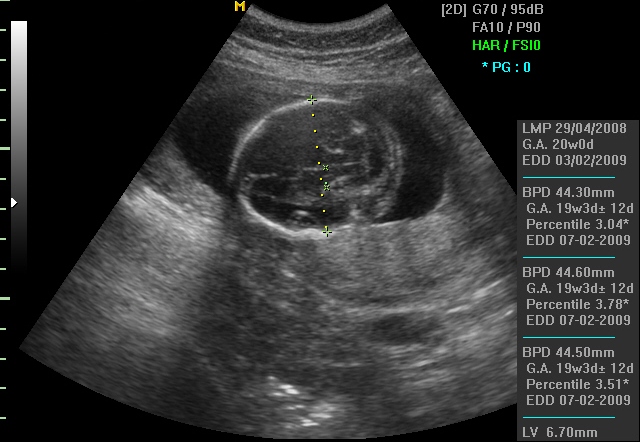

BPD (Biparietal diameter) претставува пречник на гавата на бебето, и се мери по 13. недела. Бидејќи бебиња со иста гестациска старост може да имаат различен дијаметар на главчето, оваа мерка не е многу валидна за одредување на староста на плодот.